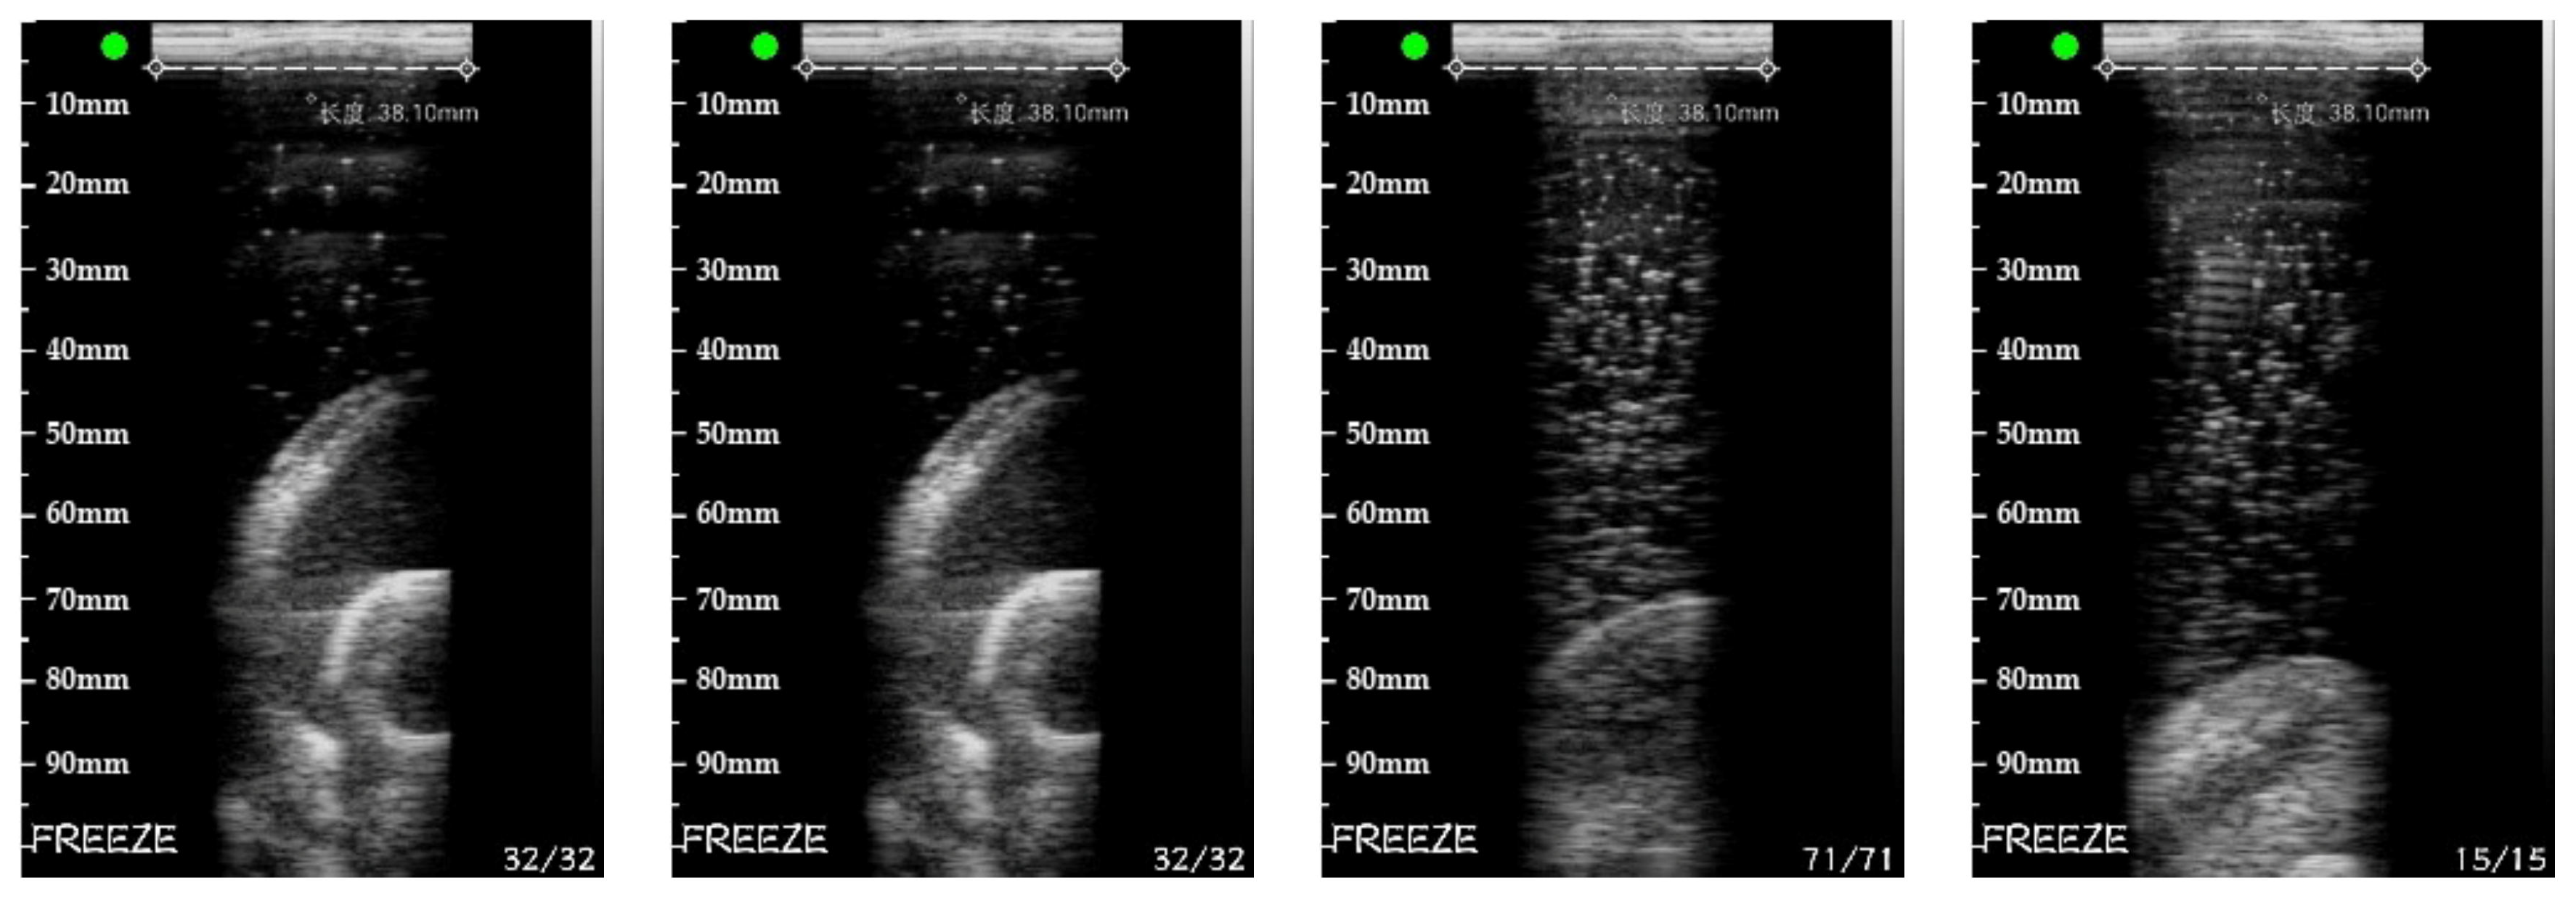

5.3. Real Target Reconstruction Result